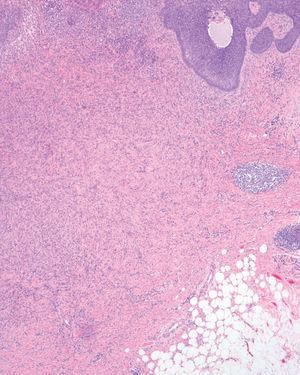

Se realizó extirpación completa de la lesión y se observó en el estudio anatomopatológico un nódulo dérmico localizado en dermis reticular, formado por una proliferación mesenquimatosa de células fusiformes sin atipias, con un patrón vagamente estoriforme. Entre ellas se apreciaban algunos histiocitos xantomizados, linfocitos y fibras de colágeno (fig. 1). Superficial a este nódulo se observó una proliferación epidérmica de células de hábito basaloide, que crecían en la dermis papilar formando pequeños nidos sólidos limitados por una capa de células en empalizada. Focalmente esta proliferación formaba nidos de mayor tamaño que infiltraban la dermis reticular. Algunos tenían degeneración quística central (fig. 2) y hendidura de separación con la dermis adyacente (fig. 3). Los cambios descritos en la epidermis eran idénticos a los observados en el carcinoma basocelular, y la proliferación fibrohistiocitaria presente en la dermis era diagnóstica de dermatofibroma.

Fig. 3.--Hendidura de separación entre el nido de células basaloides y la dermis adyacente. (Hematoxilina-eosina, x100.)

Las hiperplasias simples y proliferaciones basaloides muestran una escasa inmunopositividad para p53 al igual que la piel normal. Por el contrario, los carcinomas basocelulares muestran una sobreexpresión de p53 15. Las técnicas inmunohistoquímicas no suponen una ayuda definitiva a la hora de confirmar la naturaleza benigna o maligna del proceso 2. Se observa hiperplasia folicular de células basaloides hasta en el 23 % de los dermatofibromas en algunas series 3. Parece ser que la edad joven, la localización en el tronco y el tipo hipercelular de dermatofriboma son factores que están relacionados. La imagen anatomopatológica descrita en la literatura médica corresponde a nidos aislados o masas de células de hábito basaloide localizados en la unión dermoepidérmica o que se infiltran ligeramente la dermis y en ocasiones se continúan con el infundíbulo folicular. Se aprecian distintos grados de diferenciación folicular, incluso con aparición ocasional de verdaderos folículos en miniatura 1,3. Es característica la condensación focal del parénquima en torno a la proliferación celular que remeda al bulbo piloso 6. En algunos casos se puede observar una hendidura entorno a las masas celulares similar a la que se describe en el carcinoma basocelular, como retracción artefactual 1,3.